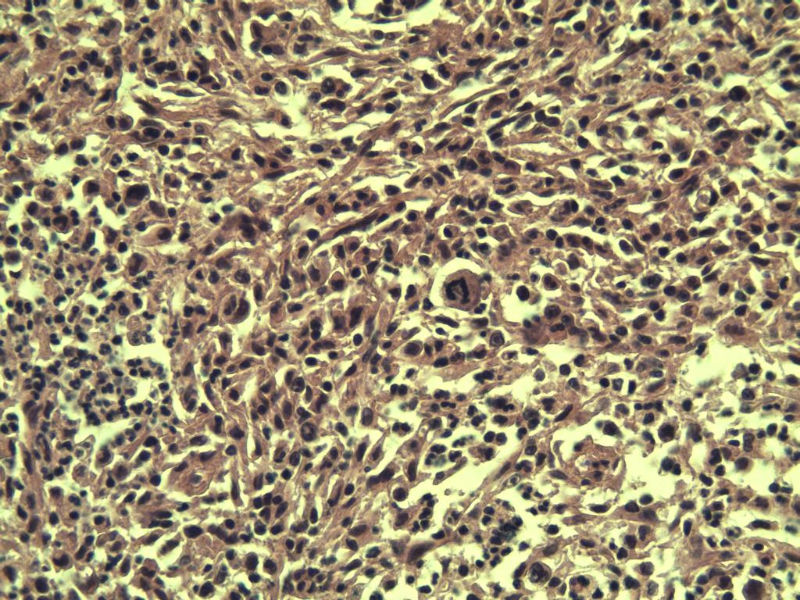

男,38岁,腹股沟 多枚淋巴结活检  直径 0.2-0.5 请各位老师看看 是什么 谢谢了!

"畏寒,发热咳嗽1年,加重伴腹部疼痛2月" 2月前患者感腹部疼痛不适伴大便呈稀大便,量不详,伴腰骶部疼痛,胸片:纵膈及右肺门多发性淋巴结肿大,进一步完善胸部CT:右肺及中叶病变,纵膈及肺门多发淋巴结肿大,结核性可能,脾脏增大,PPD(-),1个月来患者出现中上腹食欲不振,体重进行性消瘦,全身疲乏无力,3天前到医学院就诊,腹部B超:右肝囊肿,胆囊壁毛糙,脾大,胰周多个减弱回声,淋巴结不能除外,腹水,血常规示:WBC16.36x109 /L,N%14.25%,RBC2.63x1012/L ,HGB 66g/L 。右侧腋窝及腹股沟可扪及多枚淋巴结,压痛,无明显粘连。

腹股沟 多枚淋巴结活检图4

副皮质区增生,纤维化显著,细胞呈多形性,有一些多核巨细胞及一些异型细胞,病理性核分裂易见,胞浆红染,散在的小淋巴细胞,T细胞淋巴瘤不能除外,树突细胞肉瘤等鉴别。免疫标记。CD21、CD3、CD5、CD10、CD20、CD79a、PD1、CD68、CXCL13、KI-67、CD68、CD163等,据切片选择。不知对否。

淋巴结正常结构破坏,可见大的异型细胞,上皮样或梭形,恶性肿瘤,依据病史,首先考虑淋巴造血系统疾病,大中小细胞混杂,大细胞多,形态多样,可见多核瘤细胞,除以上考虑外需鉴别间变大、组织细胞肉瘤、指状突/树突细胞肿瘤、HL等,还需排除肉瘤或癌转移,尽管病人年轻,加上ALK、CK、S-100、CD1a。